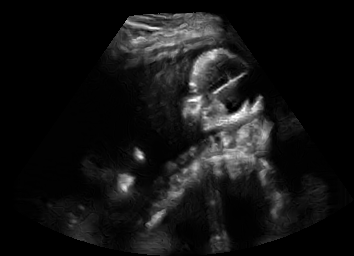

US simulation. We used a ray-tracing framework to render B-mode images from a geometric fetal model, by simulating a convex probe placed at multiple locations and orientations on the abdominal surface, with imaging settings listed in Tab 1. At each location, simply rasterizing a cross-section through the triangulated anatomical surfaces at the ultrasound center imaging plane provided corresponding semantic maps. Fig. 3 shows example B-mode images with corresponding semantic maps. A total of simulated frames were resized to and randomly split into training-validation-test sets by 80-10-10%.

In Fig. 3 we show that only learning an auxiliary seg-to-real translation, i.e. CUT+S, cannot guide the network to learn the semantics of simulated images.

CUT+SC with the loss term largely reduces hallucinated image content, although it still fails to generate fine anatomical details. With the multi-domain conditional generator and additional losses of ConPres, translated images preserve content and feature a realistic appearance. Training without leads to training instability.

Comparison to state-of-the-art. As seen qualitatively from the examples in Fig. 3, our method substantially outperforms the alternatives in terms of content preservation, while translating realistic US appearance. CycleGAN, SASAN, and CUT hallucinate inexistent tissue regions fail to generate fine anatomical structures, e.g. the ribs. StarGAN fails to generate faithful ultrasound speckle appearance, which leads to highly unrealistic images. Our method ConPres preserves anatomical structures, while enhancing the images with a realistic appearance. It further faithfully preserves acoustic shadows, even without explicit enforcement. However, as seen from the last column, the refraction artefact appears artificial in the images translated by all the methods. Note that although the imaging field-of-view (FoV) and probe opening in the simulation is significantly different from the real in-vivo images (Fig. 2) used for training, our ConPres maintains the input FoV closely compared to previous state-of-the-art. The results in Tab 2 quantitatively confirm the superiority of our method. Note that SSIM and FID/KID are used to measure translation performance from two different and sometimes competing aspects, with the former metric for quantifying structure preservation and the latter metrics for image realism.